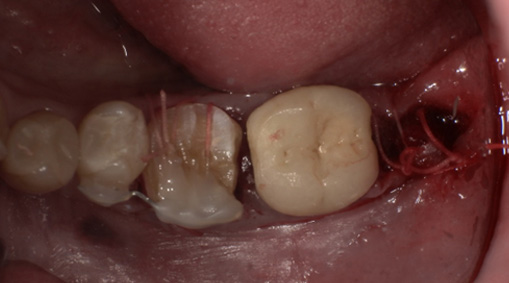

まず歯冠を切除し、疼痛がでないよう、冠部歯髄を除去してネオダイン(歯髄の鎮痛鎮静、象牙質の消毒、覆髄)を填入します。その後、粘膜骨膜弁にて完全閉鎖を行います。以下に処置の流れを示します。

歯の固定や傷口を縫合します。

4-5日目 傷の消毒・経過観察を行います。

6日目(術後3-4週目) 歯内治療を開始します。

術後4週目の移植した歯牙。固定は維持されている。

ラバーダム(ゴム製の布)を装着し、歯の中の治療をします。 -